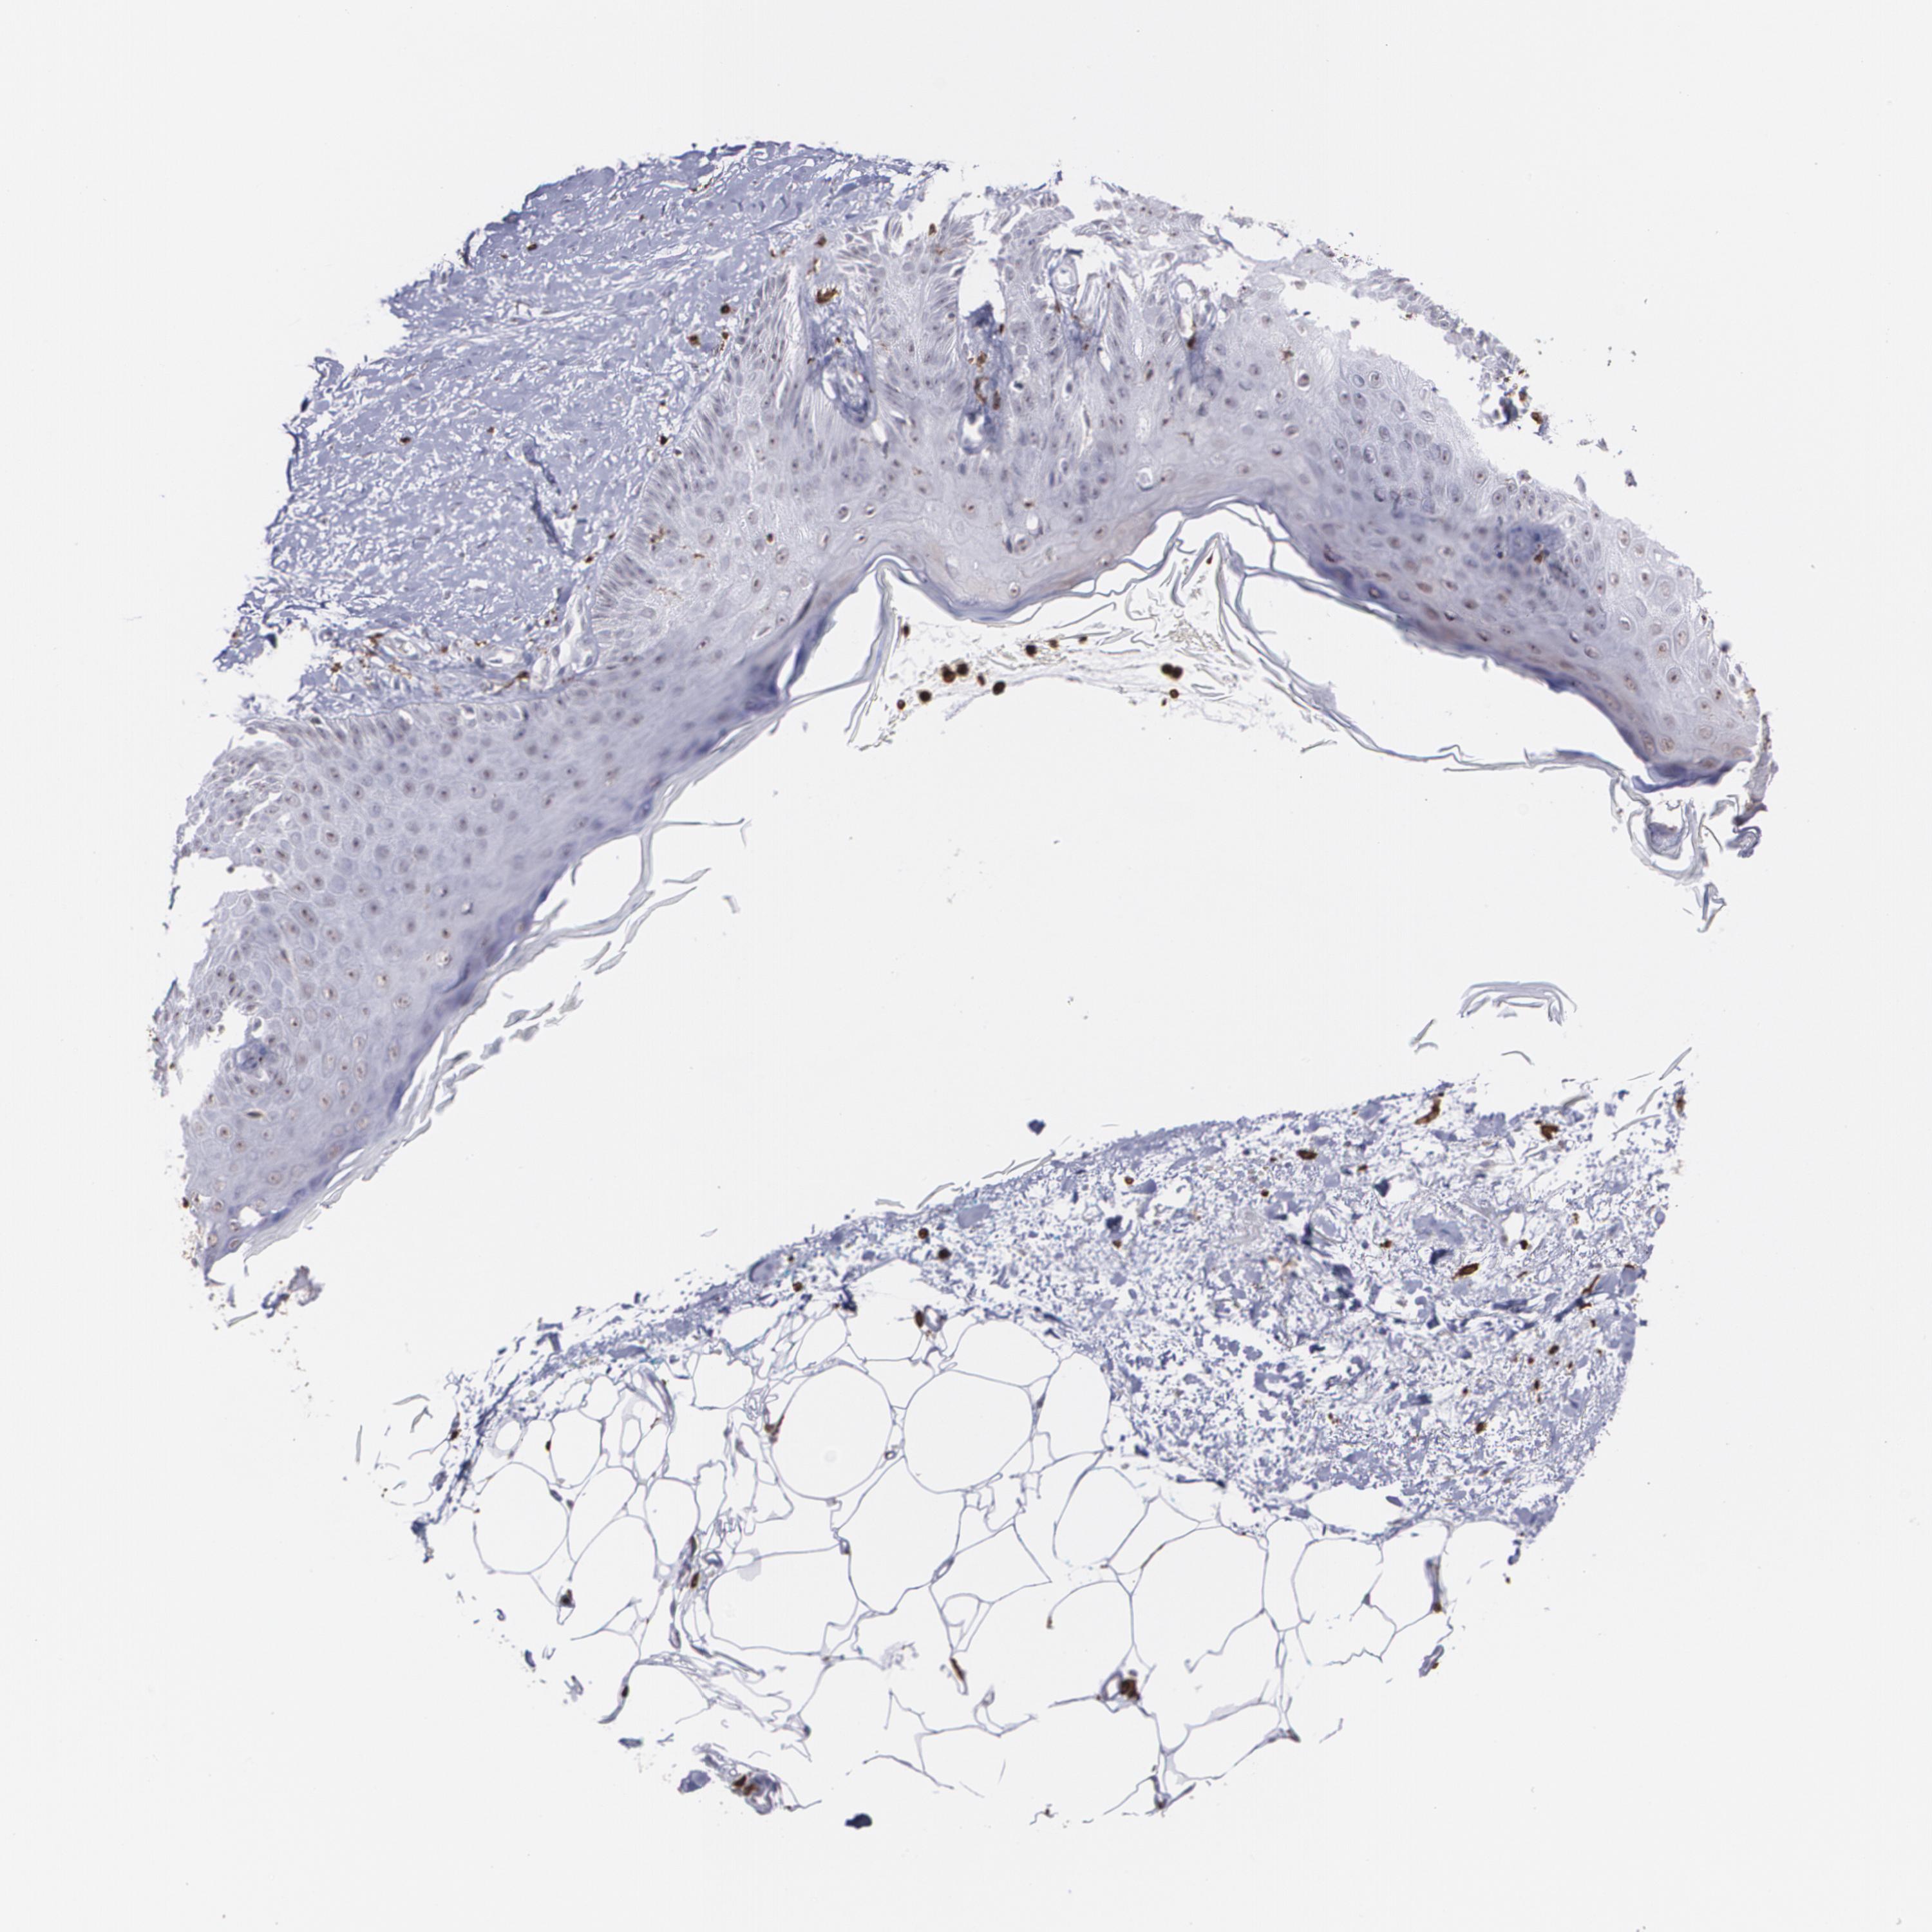

CANCER SKIN CANCER Show tissue menu

Basal cell and squamous cell cancer

SKIN CANCER - Protein expressioni

A mouse-over function shows sample information and annotation data. Click on an image to view it in a full screen mode. Samples can be filtered based on level of antibody staining by selecting one or several of the following categories: high, medium, low and not detected. The assay and annotation is described here.

Each image is clickable and will lead to virtual microscopy that enables deeper exploration of all samples and also displays staining intensity scores, fraction scores and subcellular localization as well as patient and tissue information for each sample.

Antibody HPA002327

Antibody HPA006040

Antibody CAB022160

Squamous cell carcinoma, NOS

Basal cell carcinoma